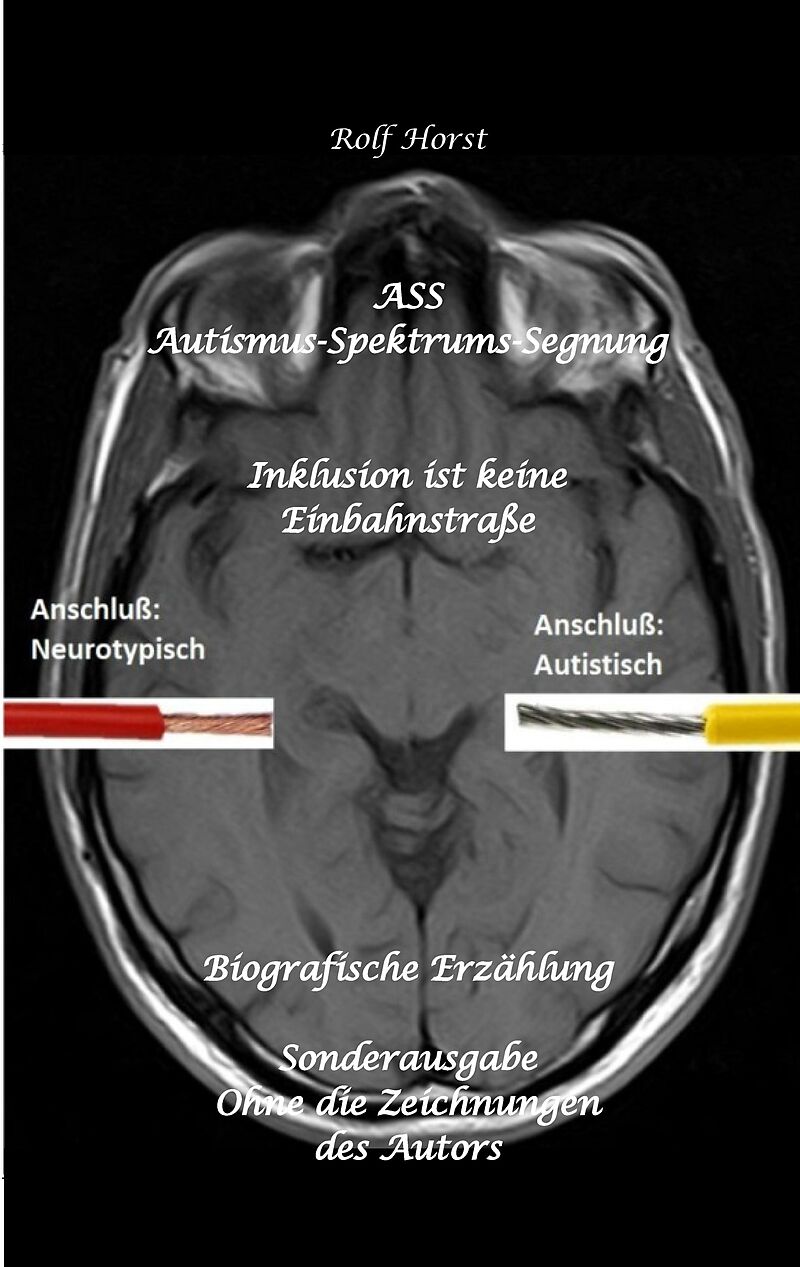

ASS Autismus-Spektrums-Segnung - Inklusion ist keine Einbahnstraße: hochfunktionaler Autismus, Mobbing, Trauma, Sucht, Häusliche Gewalt, Psychotherapie, Umzug, Inklusion, Katholische Kirche, Zen

Es handelt sich hier um die Lebensgeschichte einer heute sechzigjährigen Frau. Schon als Kleinkind geschlagen, abgewertet, ausgegrenzt und Schuld an allem, ziehen sich diese Erfahrungen in Form von permanenten Retraumatisierungen wie ein roter Faden durch ihr ...Format auswählen